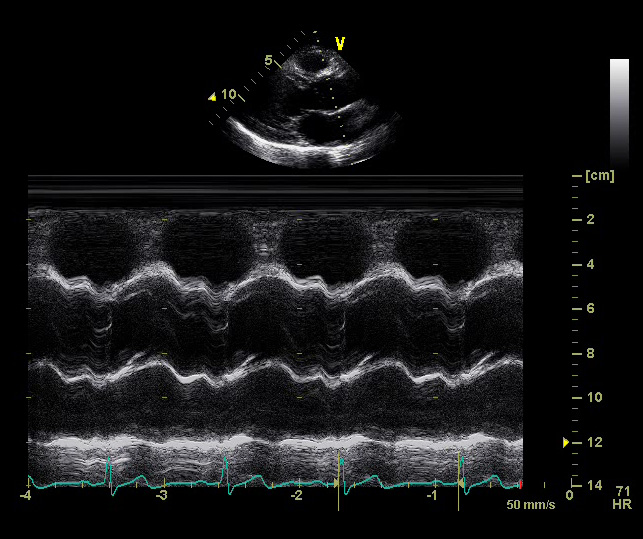

On a normal aorta valve you have three flaps which prevent the blood from leaking back into your heart when it beats. My heart is what they call bicuspid meaning I only have two of the three flaps which leaves a hole; quite a visible hole.

The doctor says that this is congenital, meaning I’ve always had it, I’m only now having some discomfort and other symptoms which caused me to see the cardiologist. From what I’ve read, surgery is the only option to fix this, and the doctor said that I will have a valve replacement in my future.